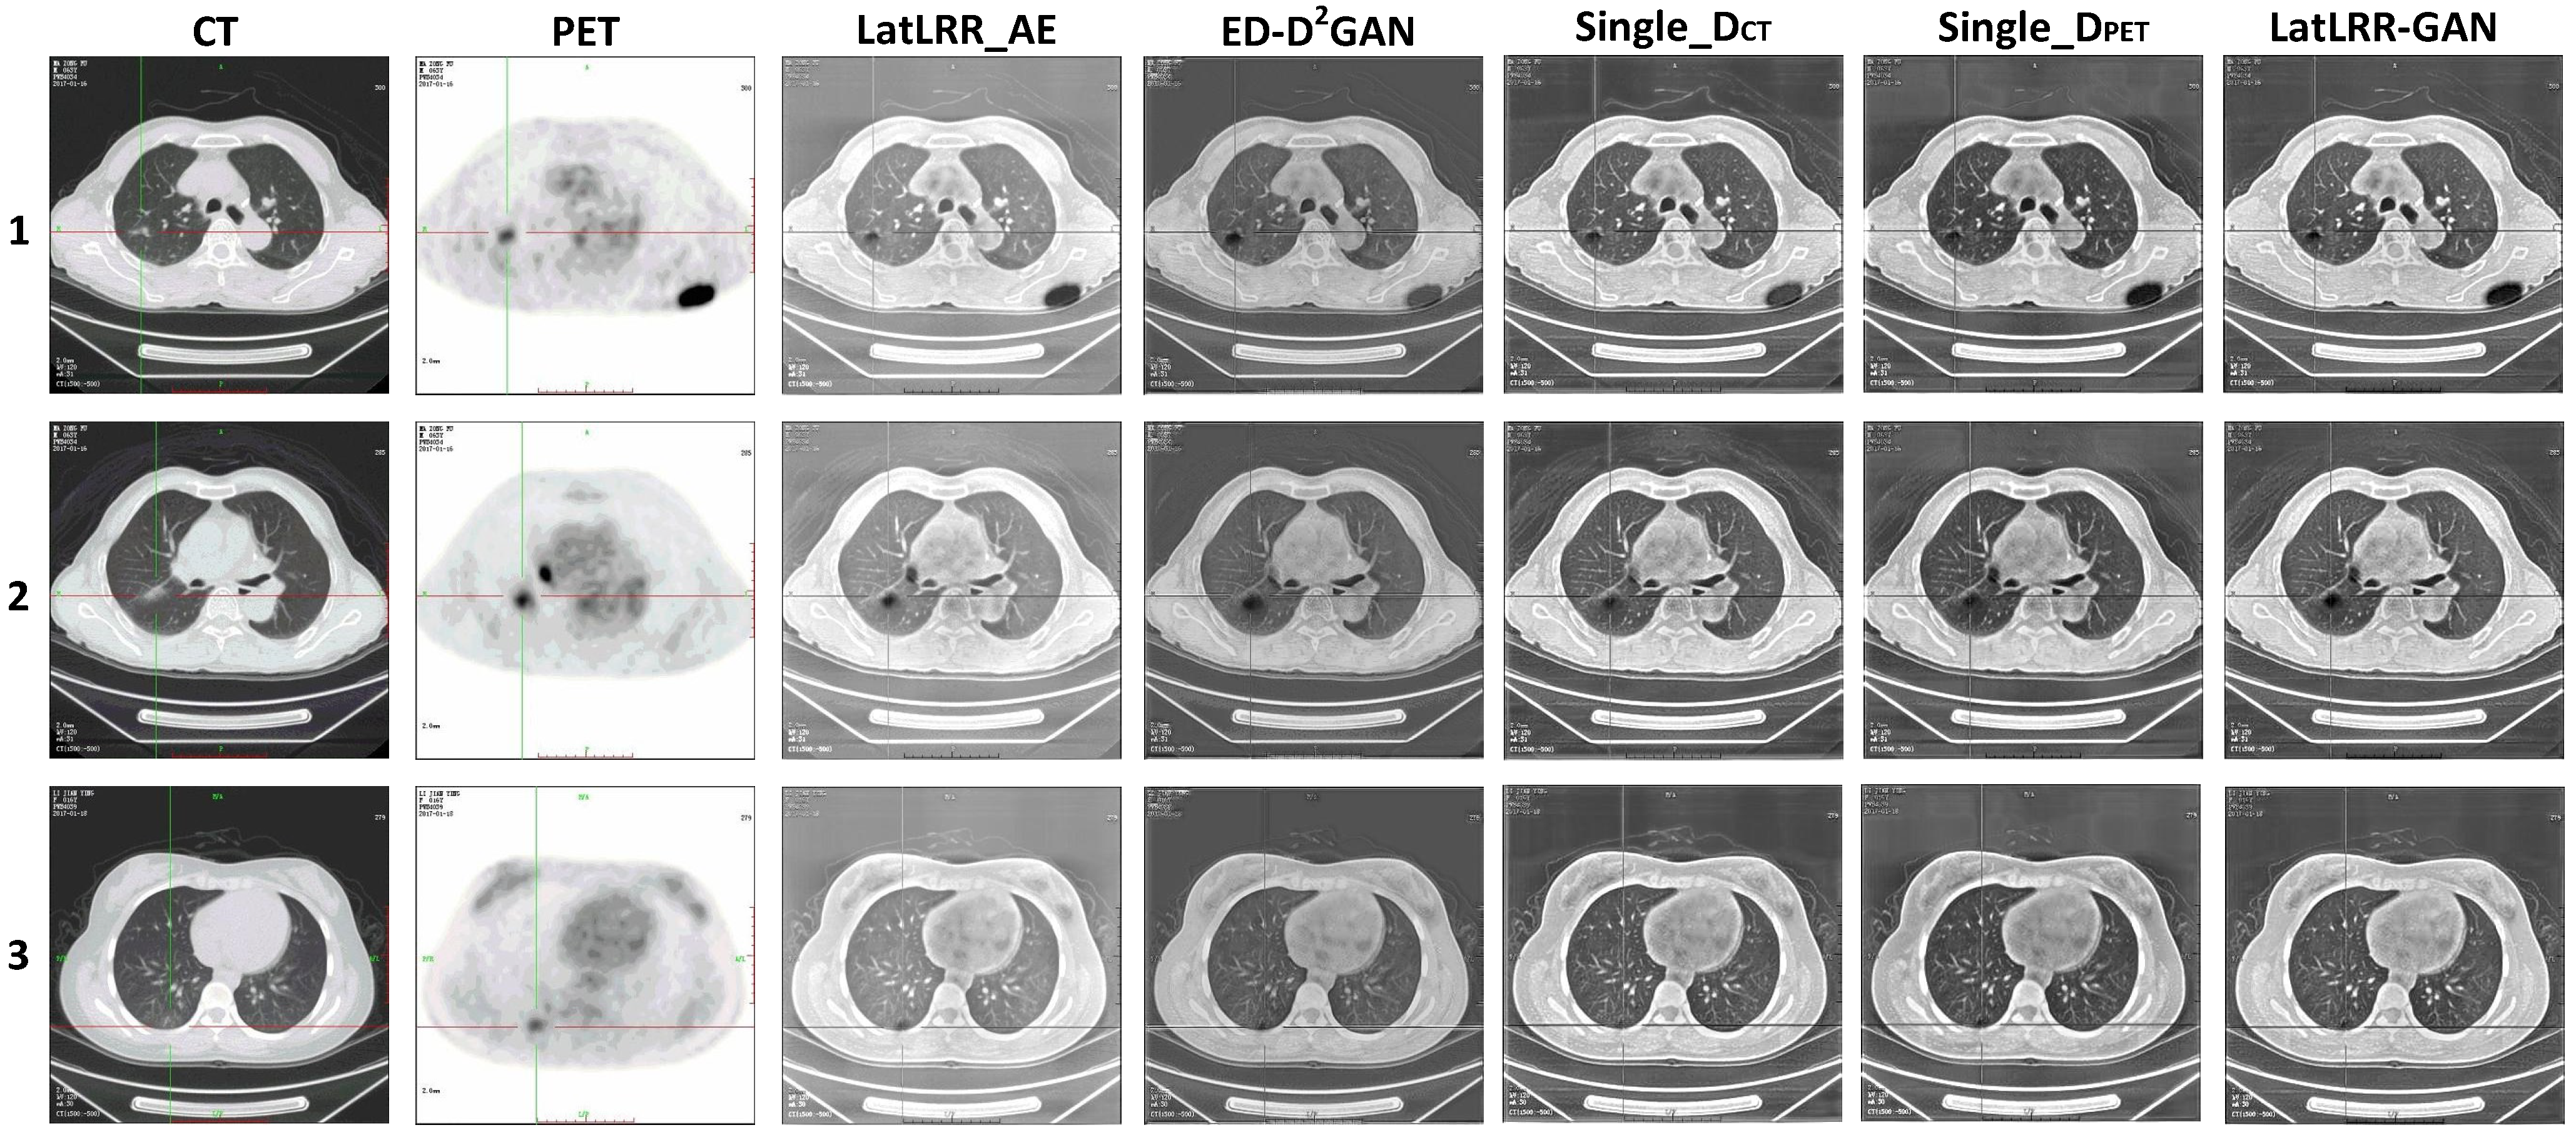

3.3.1. CT Lung Window Images and PET Images

3.4.1. CT Lung Window Images and PET Images